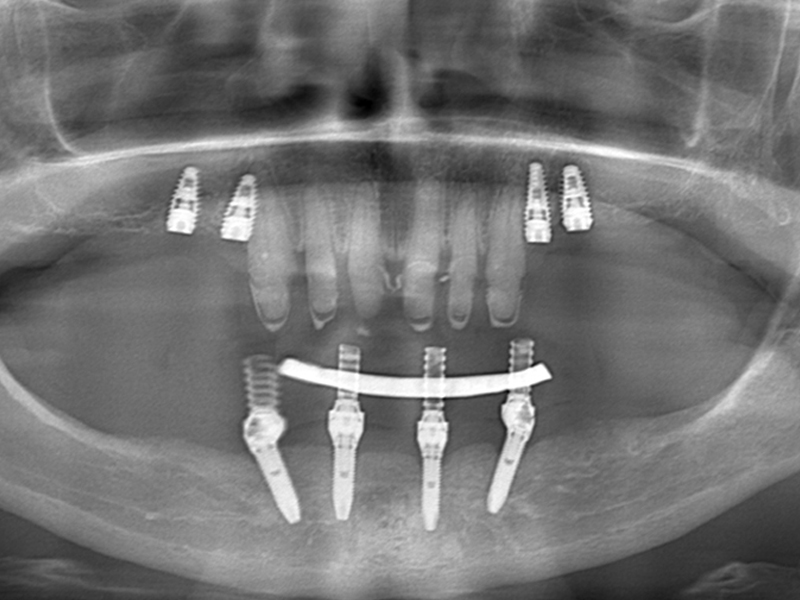

This method is aimed both at edentulous patients who want a fixed prosthetic restoration, and at patients who have an insufficient amount of bone necessary to insert implants and are not candidates for conventional implant-prosthetic therapy.

Using the All-On – 4 method; Dental implants are inserted in the same day and in a few hours, a temporary but fixed prosthetic job is performed immediately which will remain until the implants are perfectly integrated into the bone. After about 4-6 months, definitive prosthetic rehabilitation will be performed, which will be screwed onto existing implants. The screw fixing will allow you to remove the restoration (fixed bridge) when necessary.

The specificity of this procedure is that the teeth are fixed on four implants. Thanks to the particular method of inserting the implants, bone reconstruction is not necessary, which is instead a requirement when it is necessary to reconstruct in patients who have total tooth loss.

| absence of bone reconstruction |

| absence of the maxillary sinus lift and complex surgical procedures and represents a satisfactory aesthetic solution and allows correct oral hygiene maintenance. |